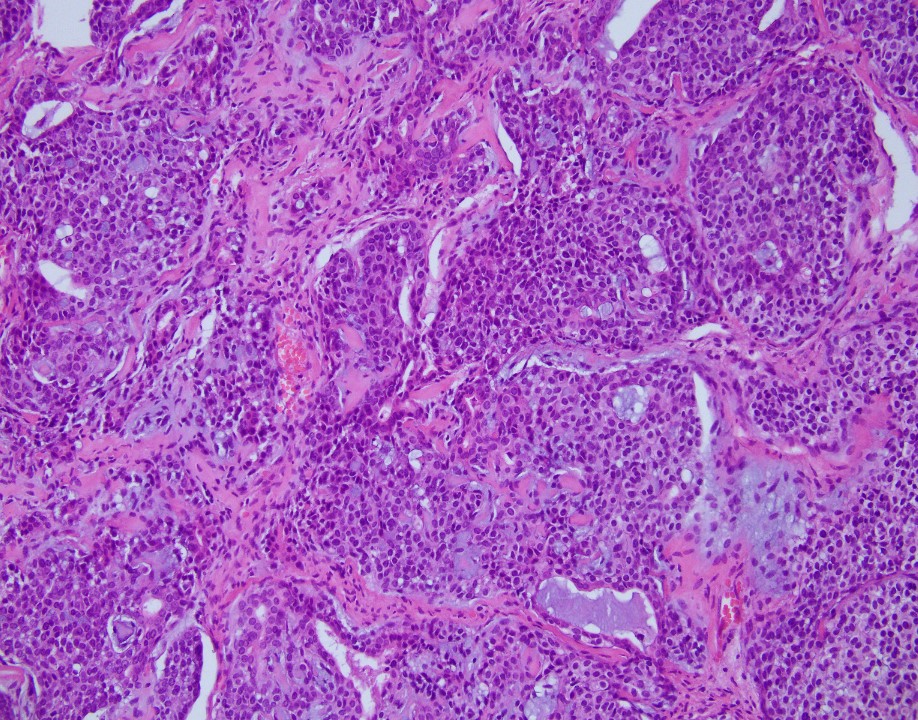

75 years old female. MR image shows a 5.2 x 4.4 x 4.0 cm perianal mass. This is left perirectal mass biopsy:

Answer: A. Adenoid cystic carcinoma

The neoplasm reveals mixed epithelial and myoepithelial components, without significant cytologic atypia, embedded in a chondromyxoid stroma. The epithelial component shows strong cytoplasmic positivity with cytokeratin (AE1/AE3), while the myoepithelial component is positive for S100 protein and p63 (with all appropriate controls). Salivary Duct Tumor Gene Fusion Analysis detected MYB-NFIB gene fusion, which supports this is an adenoid cystic carcinoma.